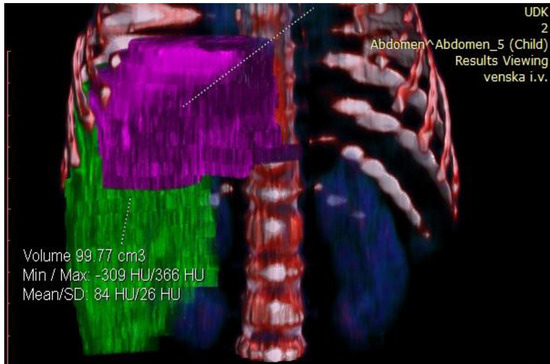

Considering the tumor’s size and localization, volumetric measurement was indicated to assess its resectability. Volumetric assessment of the liver showed that FLR was 99.77 cm3. The estimated total liver volume (ETLV) was 400.77 cm3, with an FLR/ETLV ratio of 24%, which was considered small for size after major hepatectomy and would lead to PLF (Figure 4 and Figure 5).

Figure 4.

Preoperative volumetry of the liver showing total liver volume (TLV).

Figure 5.

Preoperative volumetry of the liver showing future liver remnant (FLR).